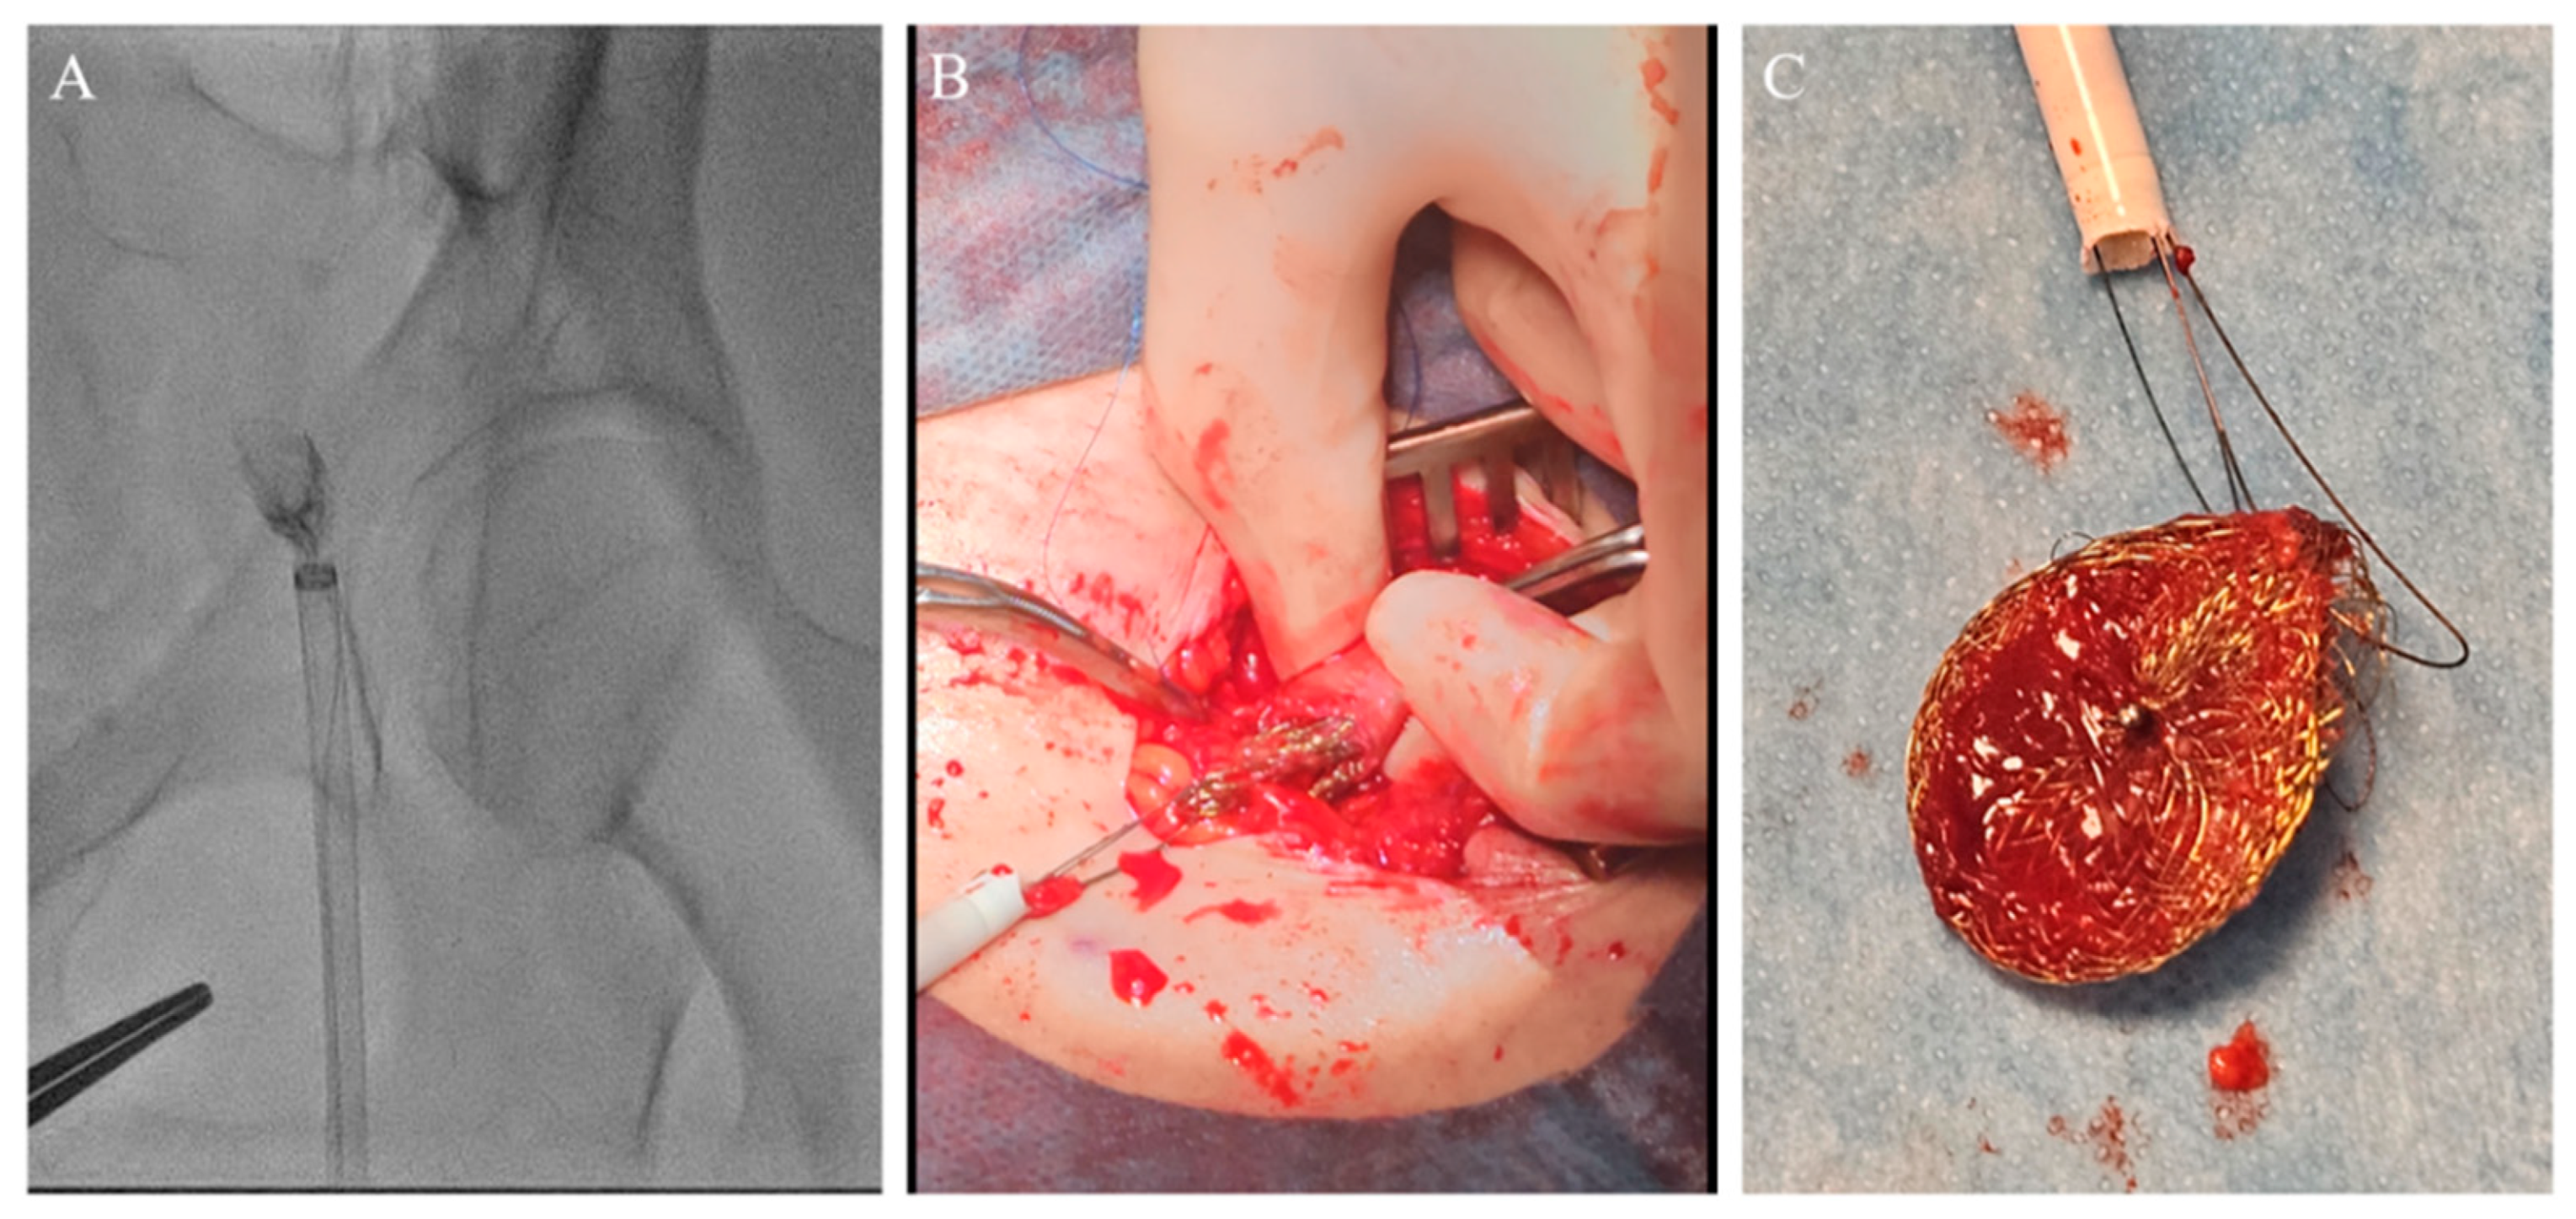

Figure 5.

Amplatz Goose Neck snare complemented with two coronary guidewires (GWs) in a unique system for occluder retrieval.

The entire wire–occluder system within the 14F introducer was then carefully retracted to the common femoral artery to a position deemed suitable for surgical extraction via arteriotomy, which was achieved successfully (Figure 6).

Figure 6.

(A) Occluder within 14F introducer at the level of the left common femoral artery (CFA). (B) Surgical extraction via arteriotomy of CFA. (C) Extracted occluder wrapped with two coronary guidewires.

The left common femoral artery (CFA) was promptly punctured, followed by the placement of a 14F introducer. Several attempts were undertaken to recapture the right atrial disc button of the PFO occluder using a 15 mm Amplatz Goose Neck snare (Medtronic, Minneapolis, MN, USA), but these efforts were unsuccessful. The position of the device, trapped within the aorta, with the right atrial disk button opposite to the aortic wall, disabled access to the device even with a 6 F guiding catheter Judkins right (JR) 4 used to navigate and reach the occluder button. This step was succeeded by the introduction of two coronary guidewires with higher tip loads, namely the Pilot 150 (Abbott Vascular, Santa Clara, CA, USA) and Samurai RC (Boston Scientific, Marlborough, MA, USA), one through the JR 4 guiding catheter already positioned and the second one directly through the 14F introducer. These wires were subsequently maneuvered, one by one, through the mesh of the PFO occluder (Figure 5). The JR 4 guiding catheter was withdrawn, and a 15 mm Amplatz Goose Neck snare was introduced through the 14F introducer. Following this, two coronary guidewires were captured proximally to the PFO occluder using a 15 mm Amplatz Goose Neck snare and subsequently pulled, facilitating the partial retraction of the PFO occluder into the 14F introducer (Figure 5, Video S1).